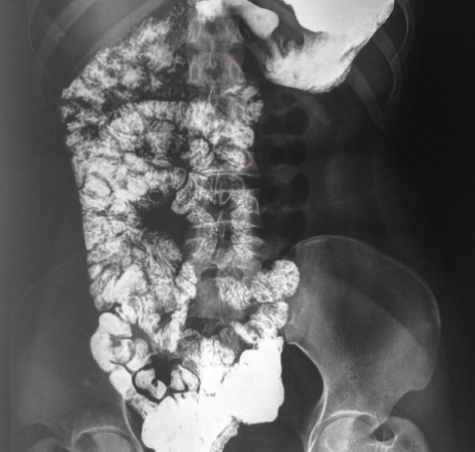

• Upper GI contrast study and US. ‘Corkscrew’

How well did you know this?